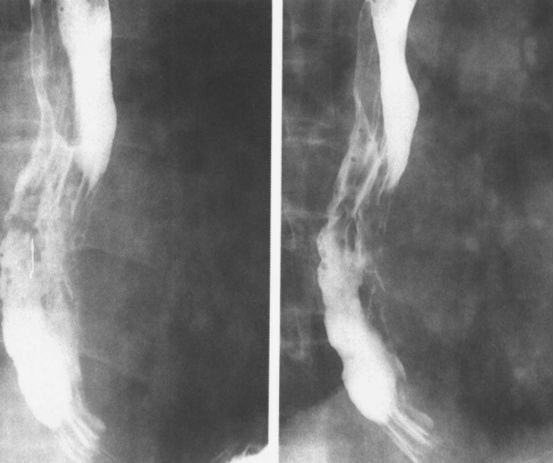

食管痉挛:螺旋状、波浪形。

食管痉挛:螺旋状、波浪状